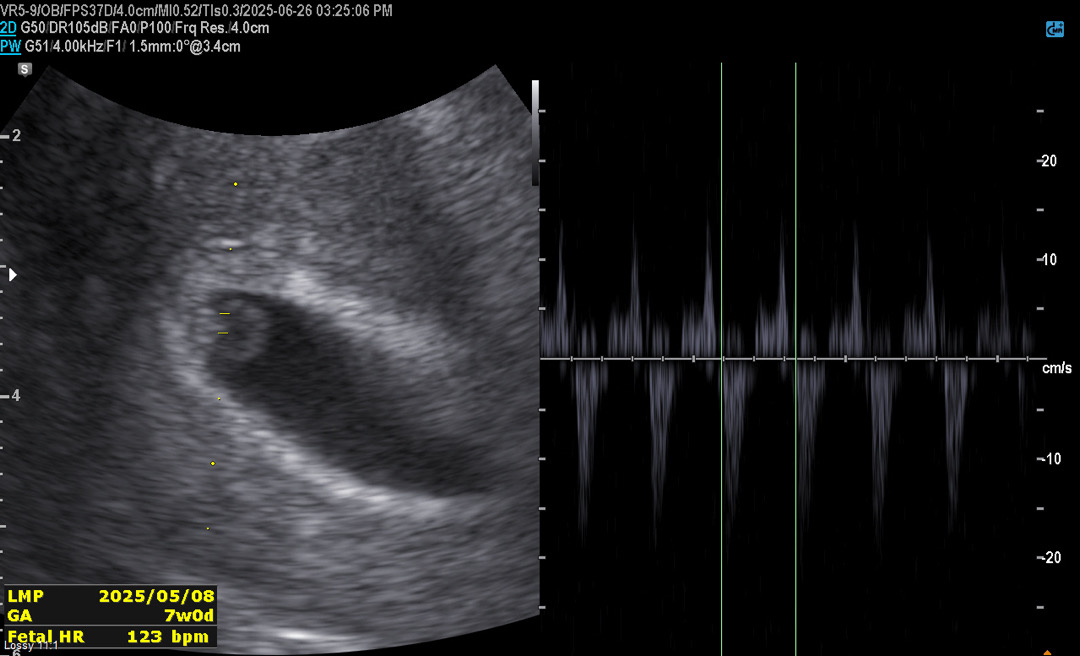

첫 심장소리

5월8일 막생 / 7주 0일차 초음파 보고 왔어요. 작년 계류유산 경험도 있고, 지난주에 피비침이 있어서 호르몬주사에 질정제 처방 받고 누워있은 지 일주일 째... 이번주 검사 가는 게 내심 두려웠는데, 처음으로 태아 심장소리도 듣고, 초기 검사도 하고 왔어요! 콩닥콩닥 잘 뛰더라고요. 123bpm으로 정상범위라는 소리가 얼마나 행복하던지..ㅠㅠ 말로만 듣던 다이아반지도 보고 왔어요. 아이가 작아서 다음주에 정확한 예정일을 알 수 있을 것 같다고 하셨어요. 일단 오늘은 기뻐해도 되겠죠? 저랑 비슷하게 아기집에 비해 태아가 작은 분들도 계실까요? 언제쯤이면 마음 놓고 푹 잘 수 있을지.. 모쪼록 다들 화이팅입니다!